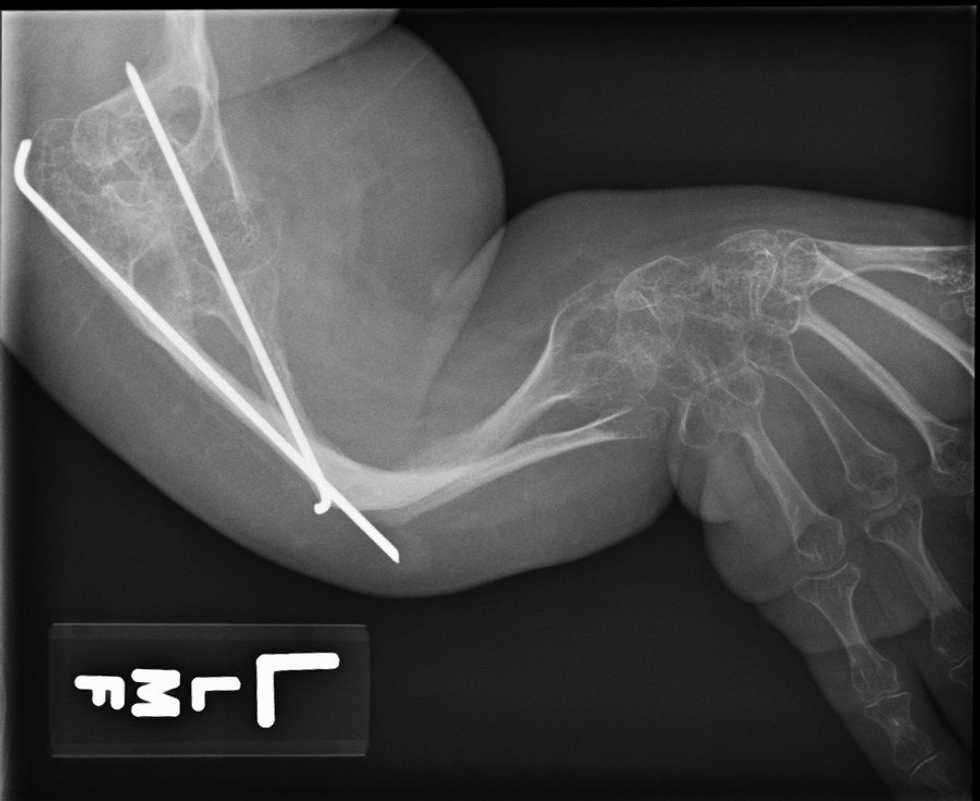

Osteogenesis Imperfecta is caused by a lack of collagen, or by your collagen being deformed or insufficient. Collagen is what makes up your hair, nails, bones, skin, basically your entire body, so it’s really important stuff. When there’s something wrong with it, you are going to have health issues that show up in one form or another. There’s vitamins and things you can take to help your body function, but the problem comes when your body has trouble absorbing any outside nutrients. It happens that OI people show collagen deficiency through brittle and deformed bones, sometimes hearing loss, bad teeth and ligament and tendon weakness.

This collagen deficiency does NOT affect nerve function at all, which means that all of my feeling receptors are very much intact. When I break a bone, depending on how bad the break is, I not only feel it, but I hear it. It can be a very loud snap, and that’s never a good sound. If you’ve ever broken a bone, you know what I’m talking about!

So yes, when I break a bone, I feel it just as much as anyone with a normal body does. It hurts, but I also have developed a fairly high pain tolerance, so I have learned how to deal with it over the years. I know what pain killers to take and when, what vitamins speed up the healing process, and what method of casting, if any, will work the best for the bone in question. Mom and I have become skilled broken bone healers!